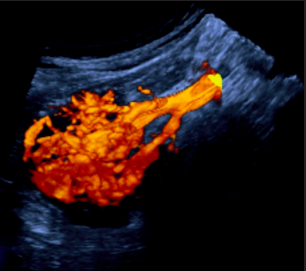

L’ECOGRAFIA NELLA VALUTAZIONE DELL’ACCESSO VASCOLARE PER DIALISI Bari – 28 e 29 novembre 2017 PROGRAMMA